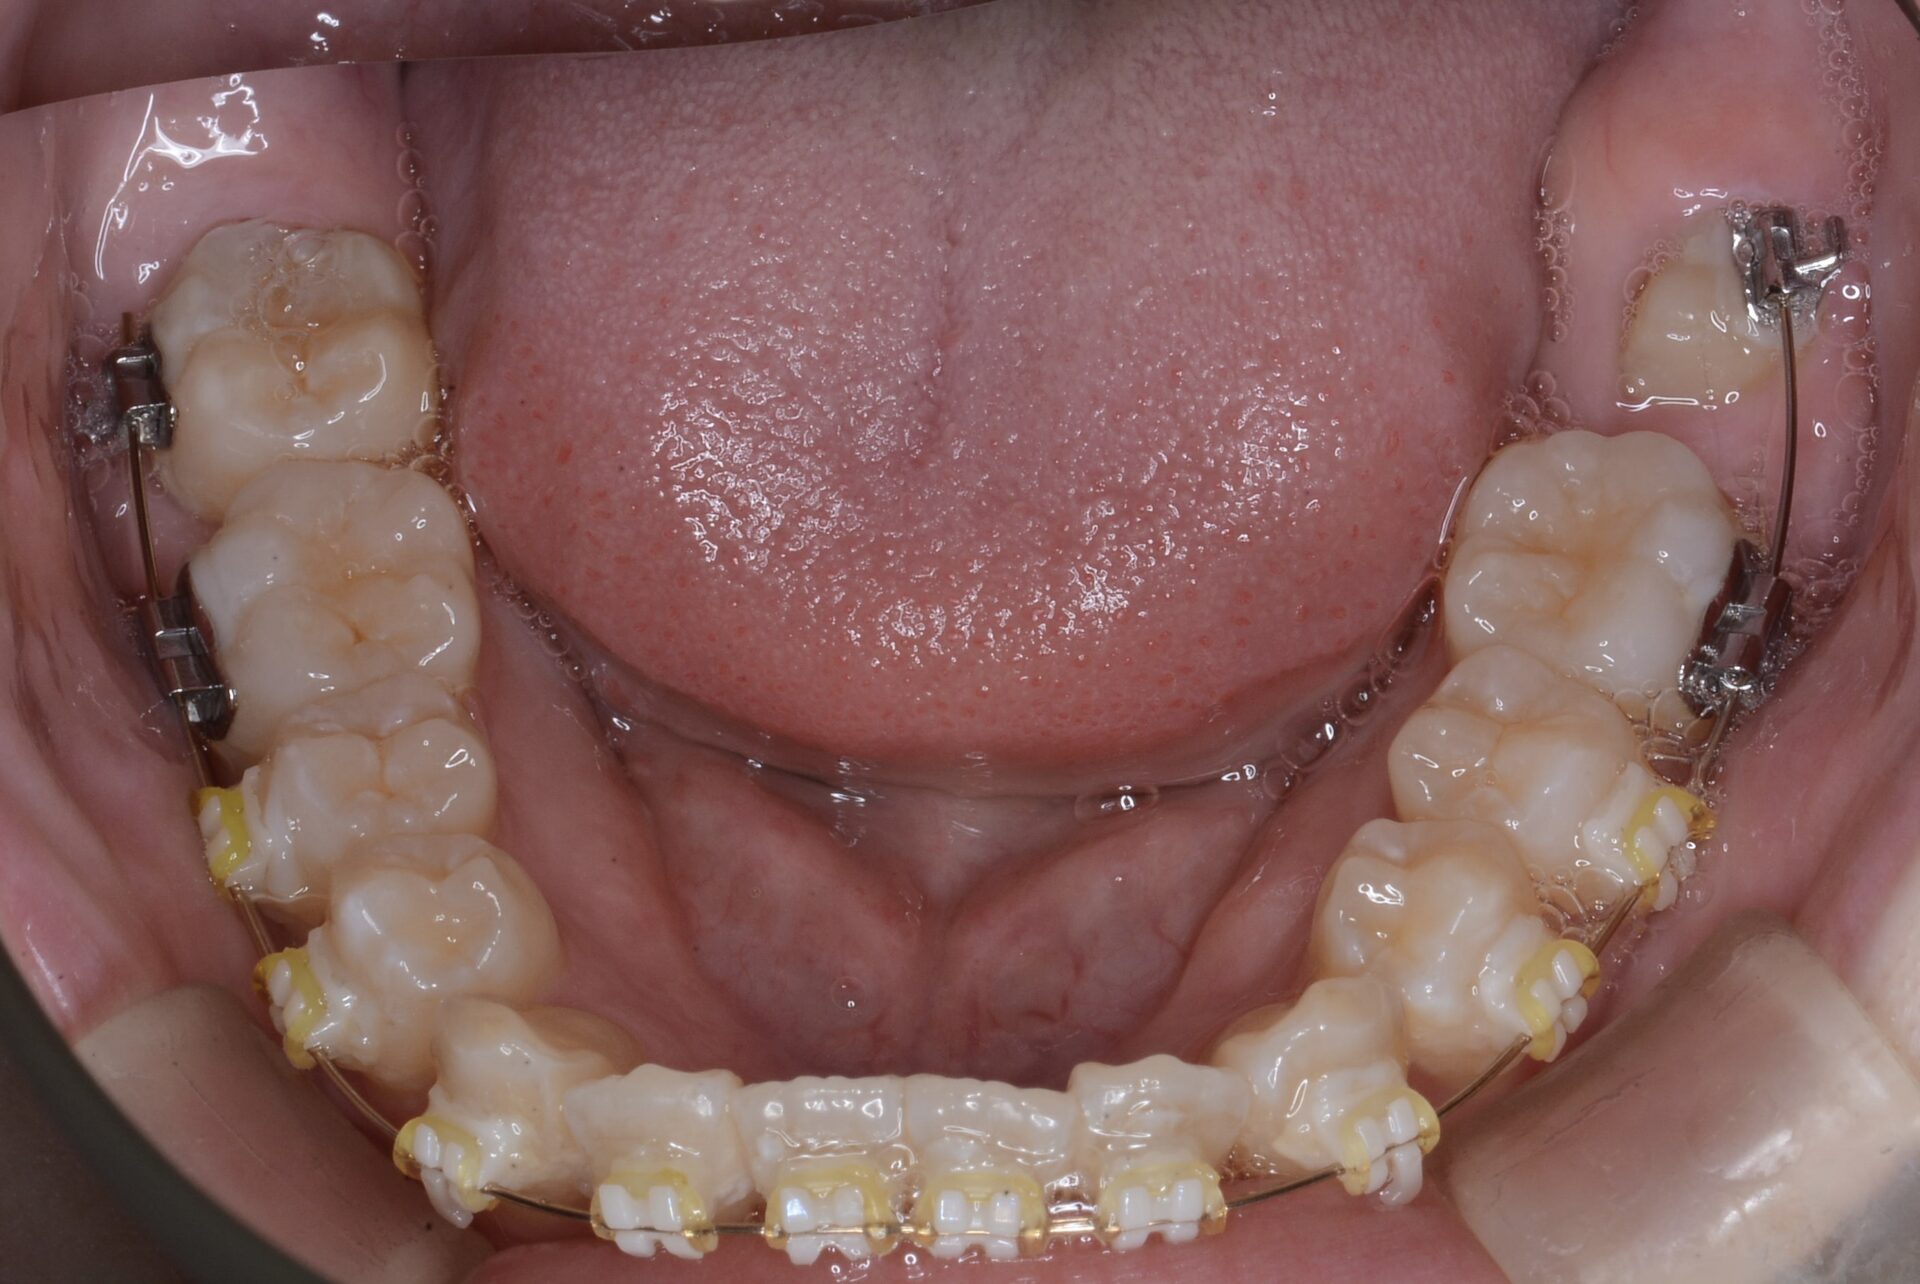

矯正治療終了時

矯正治療スタート